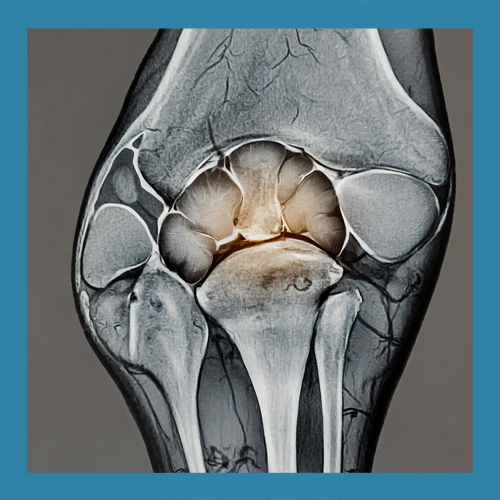

• 반월상 연골이란 무엇일까요?

반월상 연골은 무릎 관절 내에 위치한 반달 모양의 연골 조직으로, 관절 사이의 충격을 흡수하고 관절의 안정성을 유지하는 역할을 합니다. 좌우로 각각 하나씩 존재하며, 무릎이 움직일 때 발생하는 마찰을 줄이고 관절 연골의 손상을 예방합니다. 이 조직은 혈액 공급이 제한적이기 때문에 손상 시 자연 치유가 어려운 경우가 많습니다.

반월상 연골 파열의 치료는 손상의 위치와 정도에 따라 다르게 접근해야 합니다. 경미한 파열은 보존적 치료로 충분히 회복될 수 있지만, 심각한 경우에는 수술이 필요할 수 있습니다. 이를 정확히 판단하기 위해 MRI와 같은 정밀 검사가 필수적입니다.